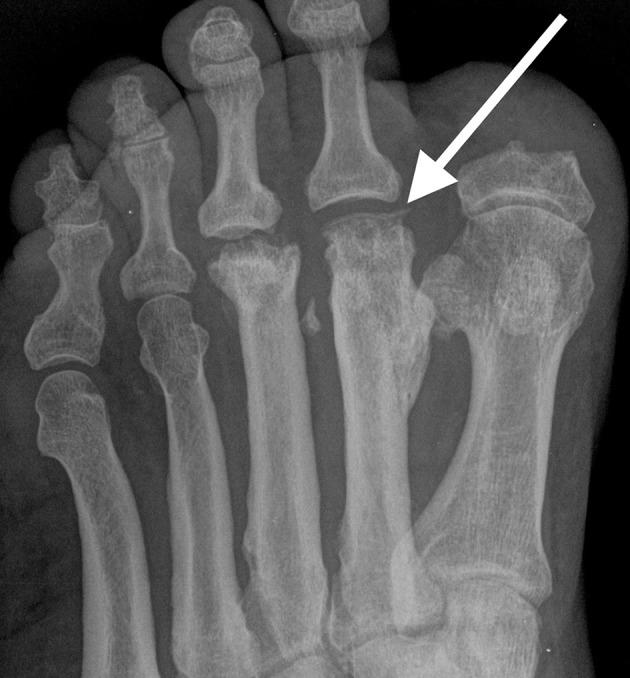

Imaging of the spectrum of bony injuries in the diabetic foot: a case series with emphasis on non-Charcot fractures.

Diabetes mellitus is associated with an increased risk of lower limb injuries. Peripheral neuropathy, often associated with diabetes, has been demonstrated to increase the risk of fracture almost two-fold and is associated with complications related to fracture healing. Detection of neuropathy-related foot injury is frequently delayed owing to the paucity of symptoms and low degree of suspicion by the clinician. Early recognition of fracture or bone injury and appropriate treatment are critical in preventing debilitating foot deformity and disability. Therefore, the astute radiologist cognizant of these potential injuries plays an essential role in early diagnosis of bony injuries in the diabetic foot. We present a series of radiological images that depict a range of osseous injuries in the diabetic foot and emphasize the role of the radiologist in early recognition of these abnormalities.

糖尿病与下肢受伤风险增加相关。外周神经病变常与糖尿病有关,已被证实会使骨折风险增加近两倍,且与骨折愈合相关的并发症有关。由于症状稀少且临床医生怀疑程度低,神经病变相关足部损伤的检测常常延迟。早期识别骨折或骨损伤并进行适当治疗对于预防使人衰弱的足部畸形和残疾至关重要。因此,敏锐地认识到这些潜在损伤的放射科医生在糖尿病足骨损伤的早期诊断中起着至关重要的作用。我们展示了一系列放射影像,这些影像描绘了糖尿病足中的一系列骨损伤,并强调了放射科医生在早期识别这些异常情况中的作用。